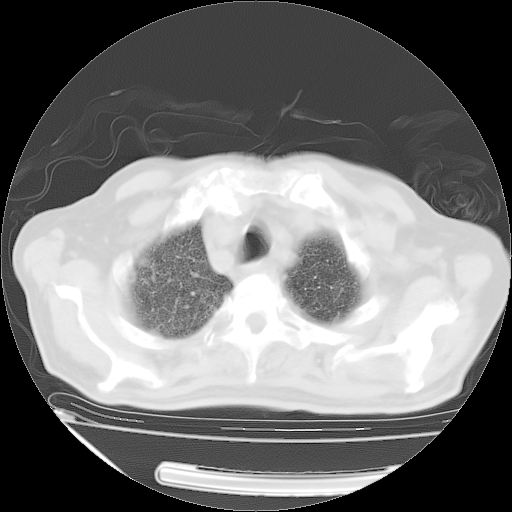

经过24天治疗,岳父的病情基本稳定。生活基本可以自理,可以下床活动。呼吸困难早已消失。体温基本正常。

只是甲强龙用80mg时血小板升到正常,改为60mg后又降到63×10*9/L。

主要治疗甲强龙80mg×14天,60mg×10天;同时抗结核(异烟肼+利福平+乙胺丁醇)。环磷酰胺0.1 tid 10天。

特别感谢胡教授、高管、桃子版主给出关键的治疗建议。桃版把所有肺部影像和全部临床资料请所在医院呼吸科、感染病科、结核科、临床免疫科专家会诊。临床免疫科专家制定了完整的治疗方案。